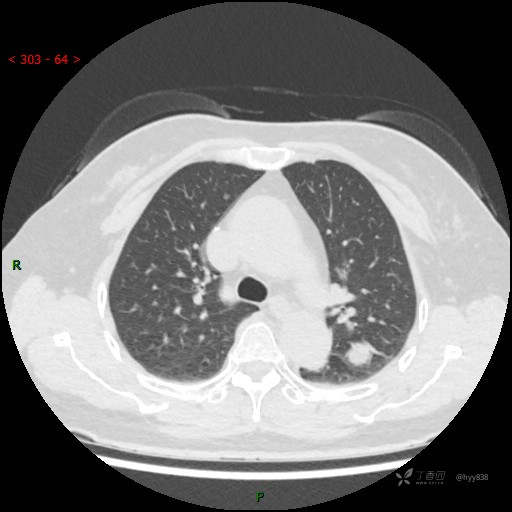

胸部CT平扫